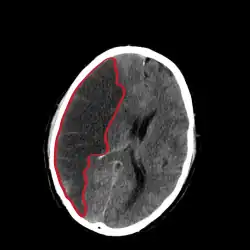

Infarkt mozku

Infarkt mozku je označován též jako ischemická cévní mozková příhoda. 80 % všech případů mozkové mrtvice je způsobeno právě infarktem. Při ischemii mozkové tkáně se rychle rozvíjí encefalomalacie, odumřelá tkáň je měkká a rozbředlá.[3] Nejčastěji vzniká v důsledku trombózy nad aterosklerotickým plátem, ale příčinou může být též rychlý pokles krevního tlaku při náhlém srdečním selhání.[3] K infarktům dochází v místech, kde se stýkají oblasti zásobované jednotlivými mozkovými tepnami a kde ischemie může přetrvávat, i když pacient přežije srdeční selhání a krevní oběh je obnoven.[1]